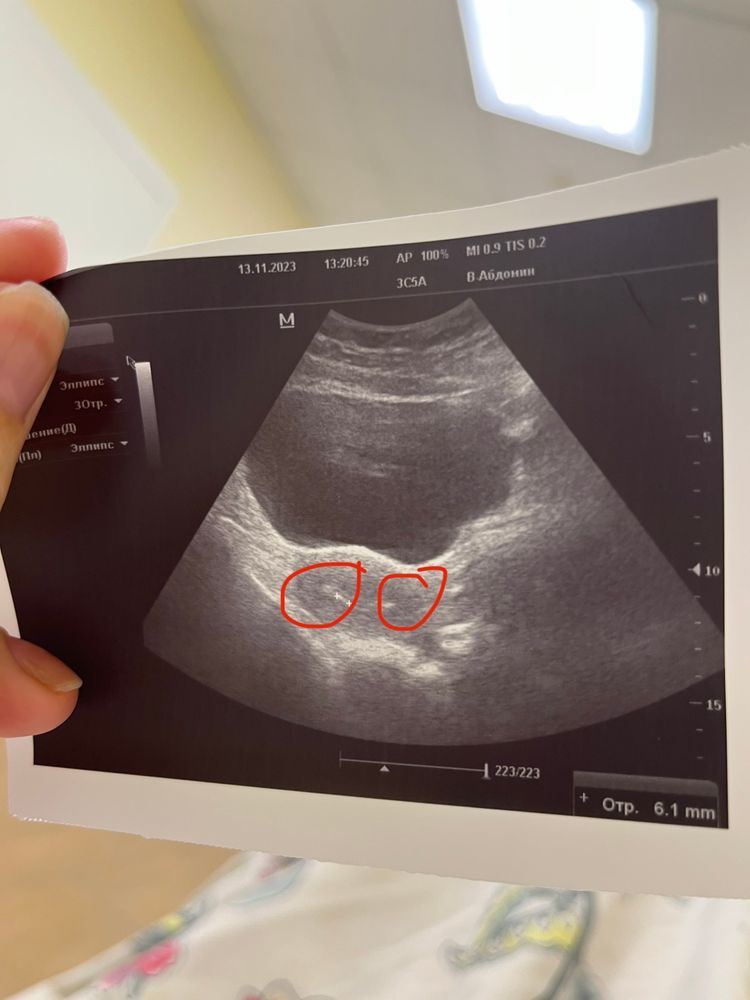

0 ДПП. Криоперенос состоятся ☺️